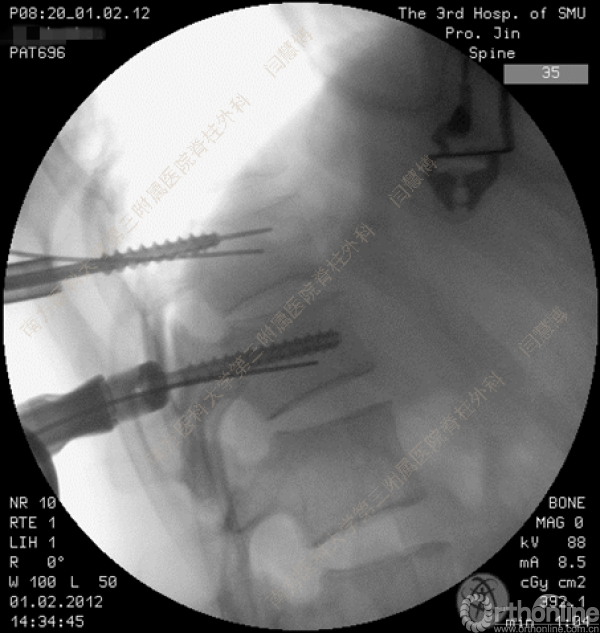

胸腰椎骨折是指由于外力造成胸腰椎骨质连续性的破坏,在如车祸、高处坠落等意外事故中,是最常见的脊柱损伤。老年患者由于本身存在骨质疏松,甚至有可能因为一些如滑倒、跌倒等低暴力因素导致胸腰椎骨折。胸腰椎骨折患者常合并神经功能损伤,且由于致伤因素基本为高能损伤,常合并其他脏器损伤,这为治疗带来了极大的困难和挑战。针对胸腰椎骨折,南方医科大学第三附属医院闫慧博教授介绍了他们运用微创方法治疗的经验。